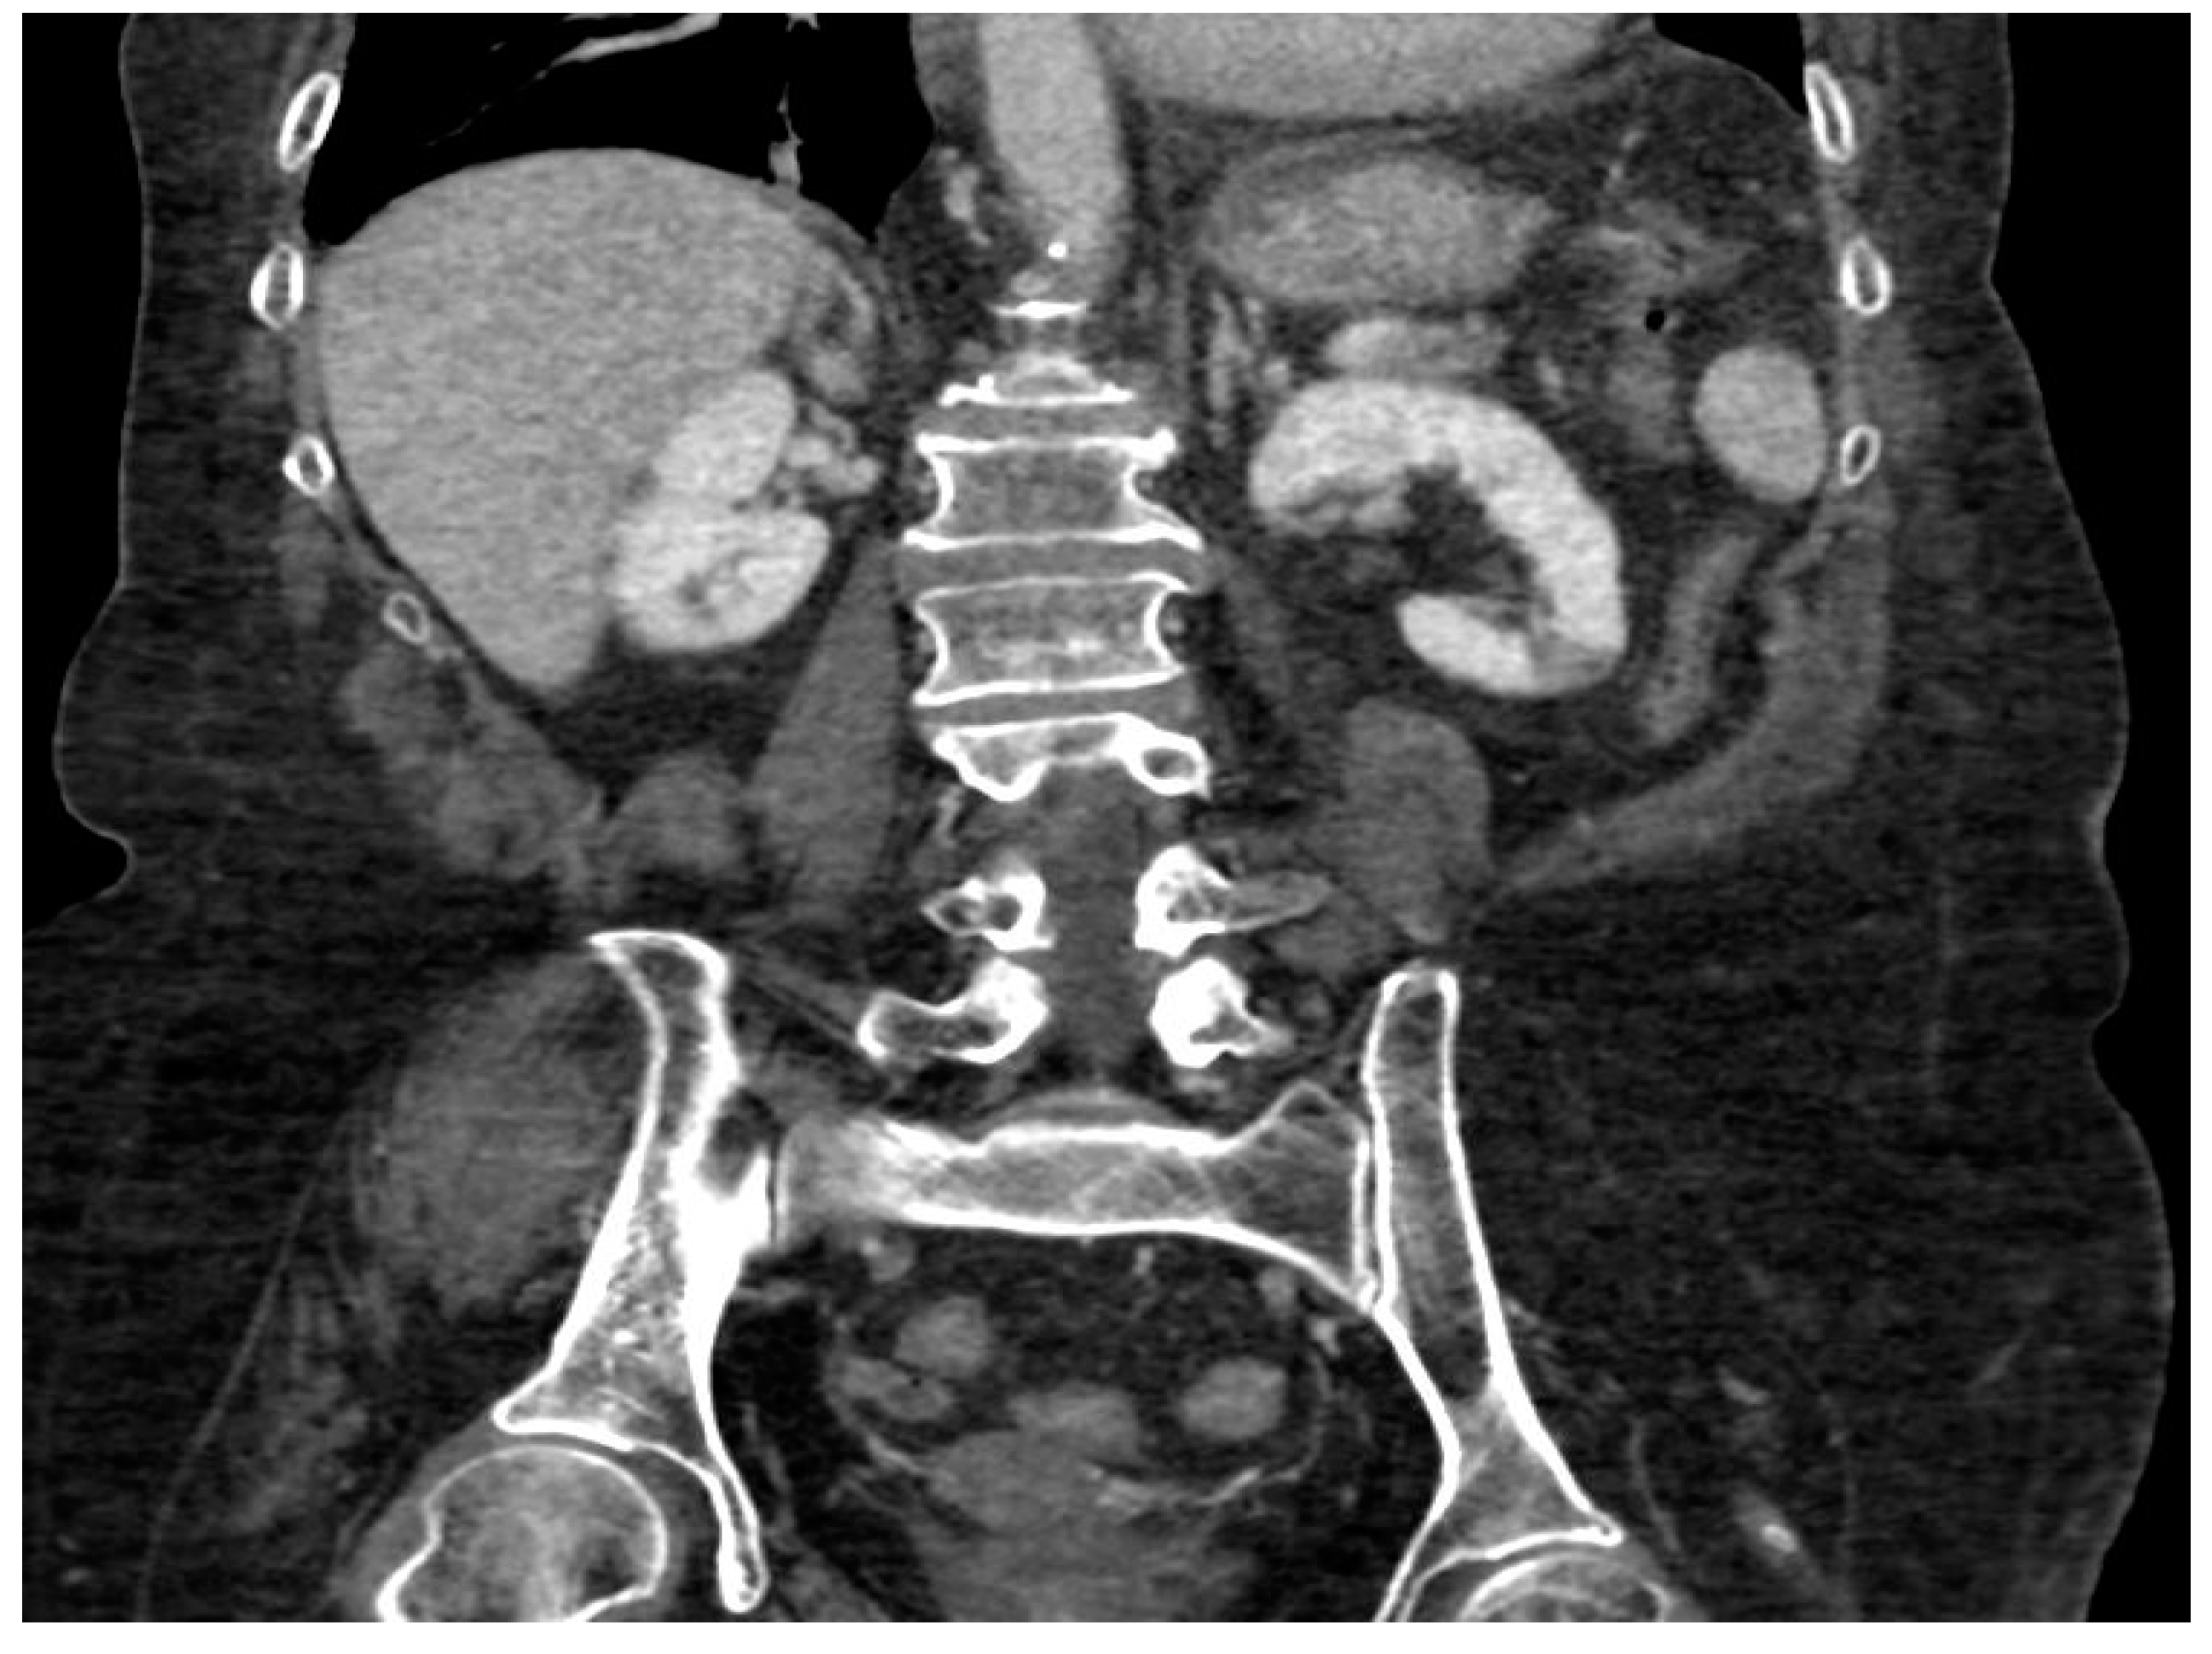

- Focal ischemia of the left renal parenchyma in four patients (36.4%) (Figure 3);